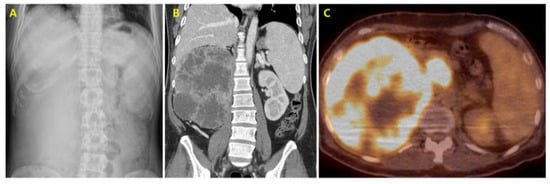

2. Case Presentation